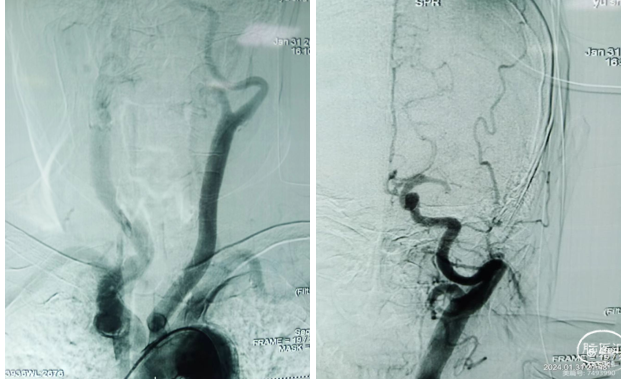

术中造影显示:Ⅲ型弓,左侧颈内C1段迂曲呈V型,C3段迂曲,C6段迂曲成环状,M1段闭塞,未向远端供血。

术前血管通路评估:Ⅲ型弓,左侧颈内C1段迂曲呈V型,C3段迂曲,C6段迂曲

成环状。